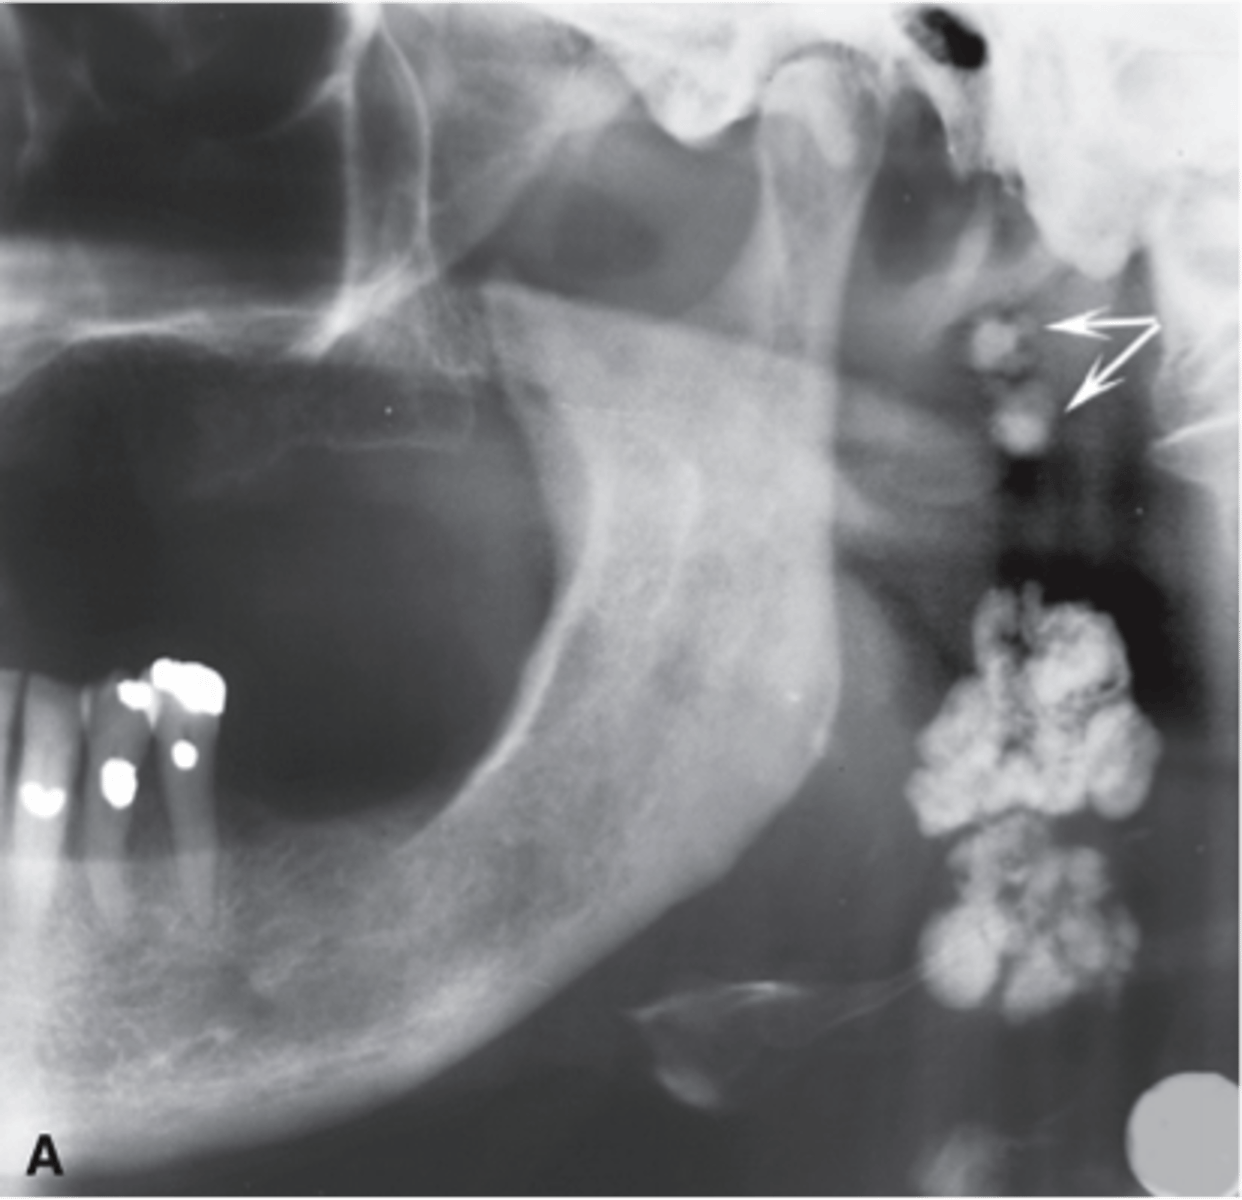

What shape do calcified lymph nodes resemble?

Cauliflower shape

Where do calcified lymph nodes typically appear?

Angle of mandible